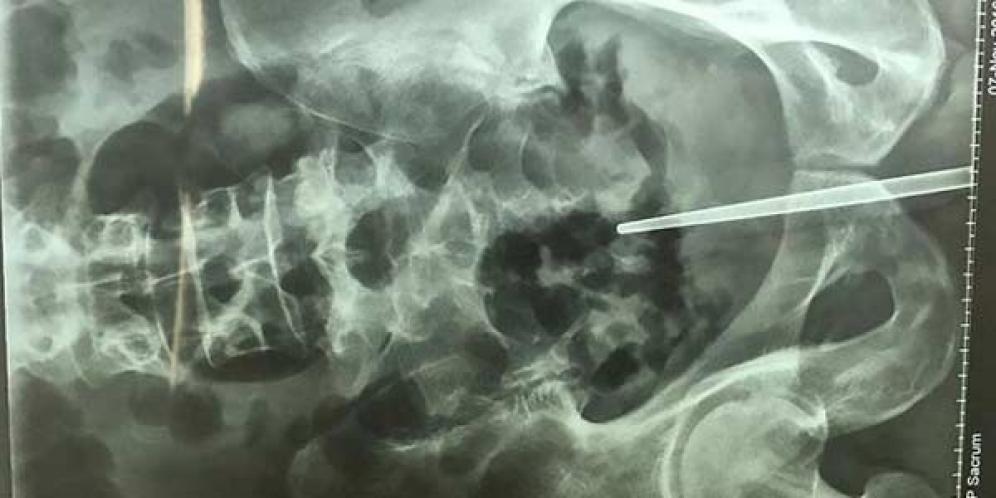

Dokter Temukan Sumpit Dalam Penis Pria di China

Sebuah rumah sakit di China mendapatkan kasus yang sangat tak biasa dan mengejutkan dari kondisi fisik pasiennya. Pasalnya, setelah menjalani serangkaian pemeriksaan...